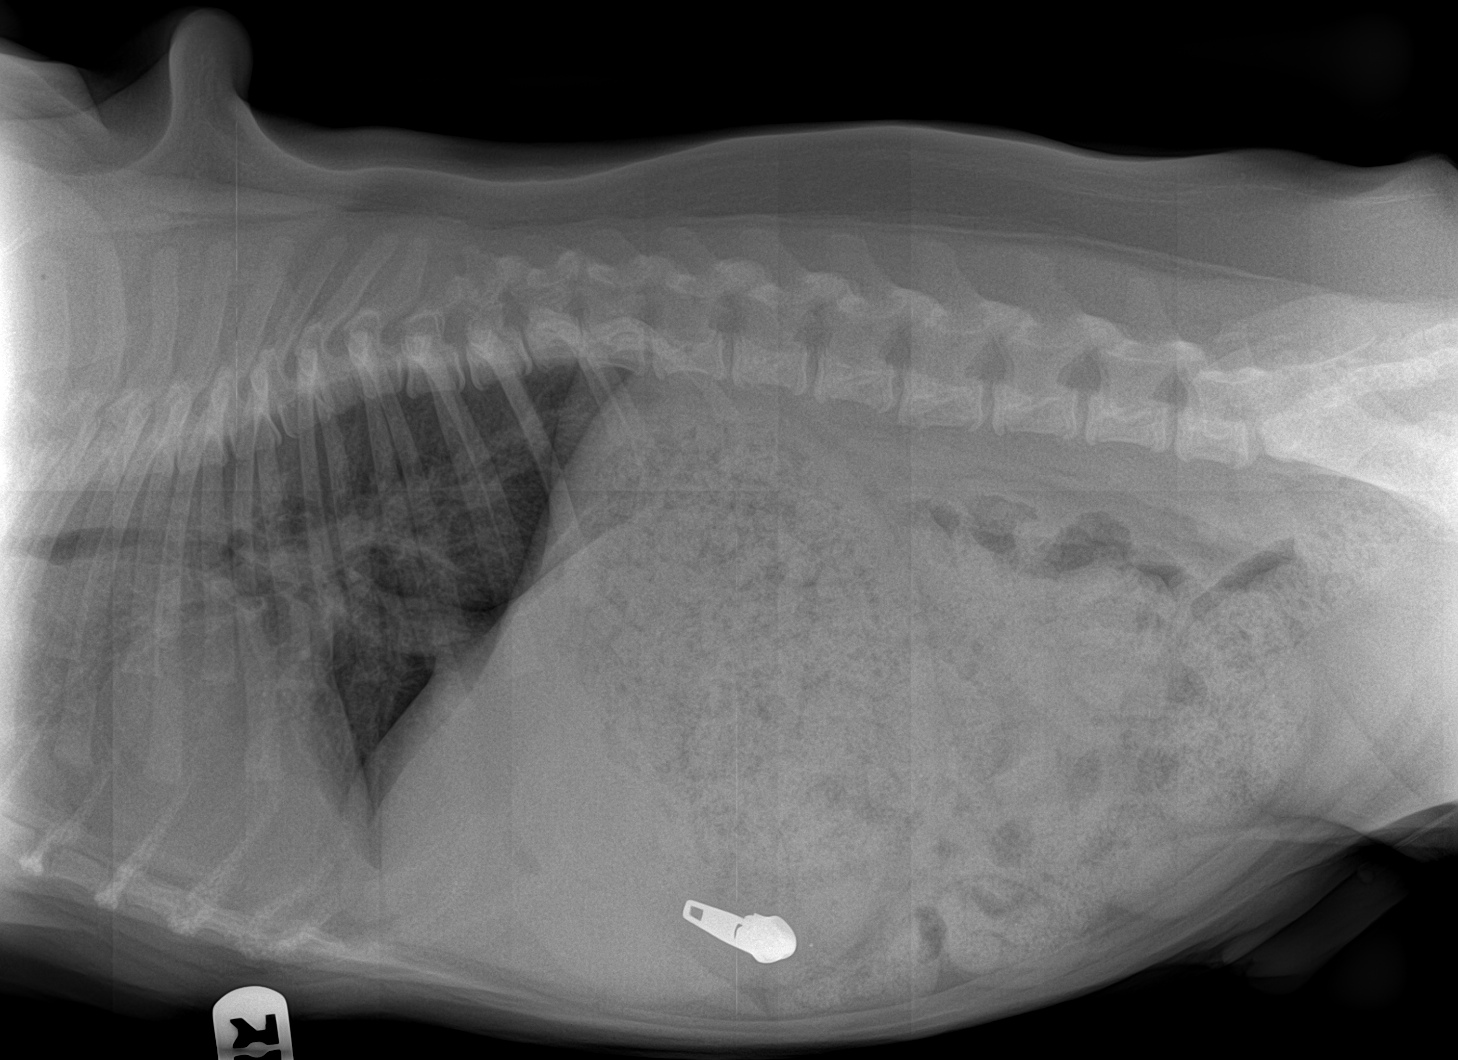

Alors, il a mangé quoi ce petit Bouledogue de 6 mois présenté initialement pour des problèmes respiratoires ?

Et oui, un bon vieux …